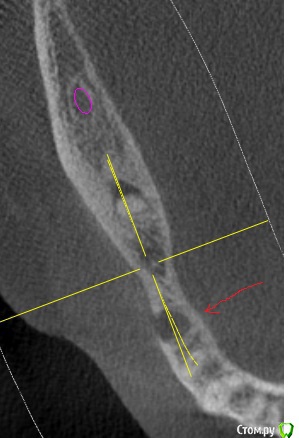

Здравствуйте.  Прошу докторов помочь советом.  Альтернатива  - либо лечить 7-й нижний с кистой (5-й под удаление без вопросов)   и ставить мост на 7-4, либо  оба удалять и ставить импланты.

Внизу пятого тоже киста (10 лет назад делали резекцию корня) или просто область с меньшей плотностью.  Эта область к сожалению выходит в сторону щеки через костную ткань ,  см. 2-й рисунок.

По срезу КТ сложно судить о кол-ве оставшихся твердых тканей зуба 47.